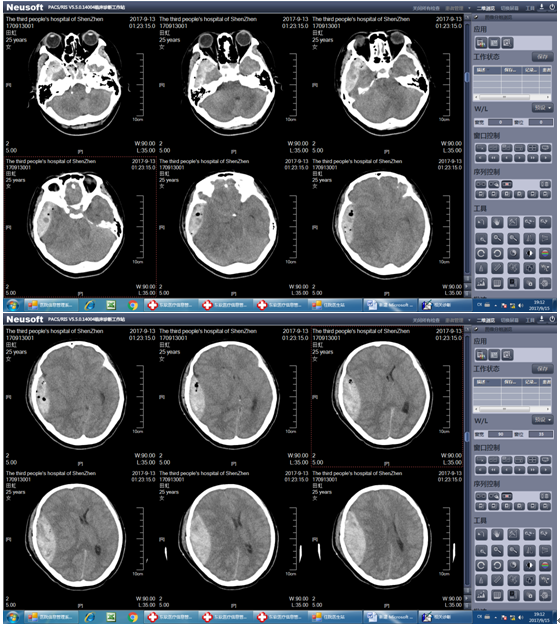

患者田某,患者于2017年9月12日23时左右过马路时不幸发生车祸,被摩托车撞伤后倒地,当即头痛,伴头晕、呕吐胃内容物多次,非喷射性。急送至我院急诊外科,查颅脑CT示:右颞顶部硬膜外血肿。入院当时患者神清,8分钟后患者病情迅速加重,陷入昏迷,呼之不应,查体先是右侧瞳孔变大,11分钟后患者双侧瞳孔直径散大直径6mm,对光反射消失,立即积极术前准备,同时急复查颅脑CT示:右颞顶部硬膜外血肿大量增加,量约90ml并脑疝形成,遂迅速启动绿色通道将患者由急诊外科直接送入手术室急诊行开颅手术治疗。

术前头颅CT